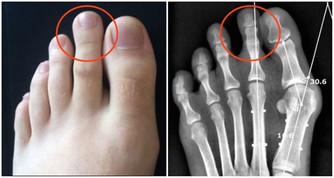

3、大魚大肉,愛喝啤酒

吃太多蛋白類食物,會產生過多的尿酸和尿素氮等代謝廢物,加重腎臟負擔。

大量飲酒容易導致高尿酸血症,這些習慣可引起高血脂等代謝疾病,引發腎臟疾病。